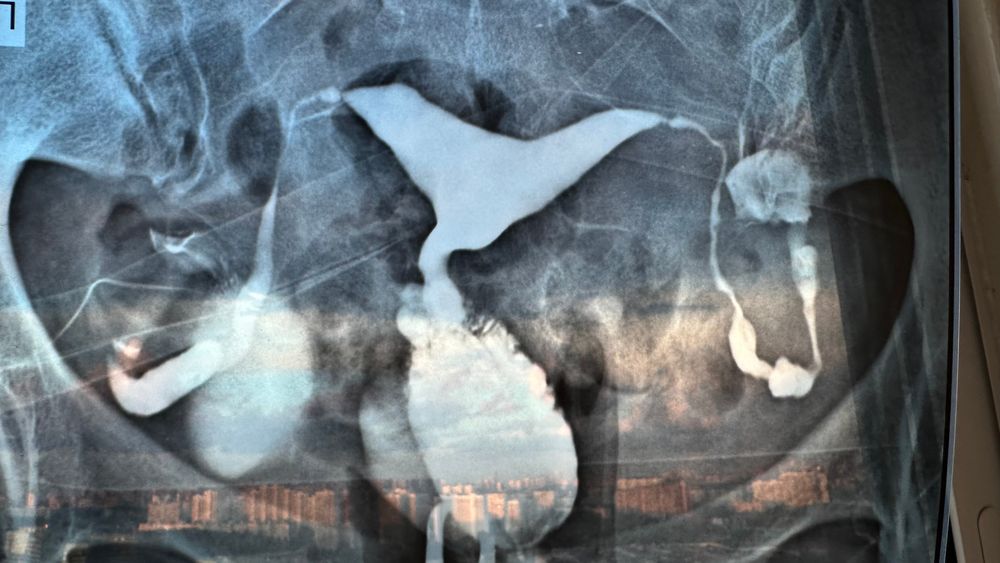

МРТ ПОСЛЕ ГСГ

Вернулись с ГСГ, состояние нормальное. Дурновато было после, то ли от объема вверенного вещества, то ли от но-шпы. Я конечно не надеялась на идеальные результаты, но думала, что все будет куда лучше

Смутили гипер эмоциональность доктора. То ему матка аномальной формы (грушевидная), то она слишком увеличенная (не беременна), а сути так и не поняла, что с ней ни так. Потом уже стало так дурно, что еле дождалась результатов и ушла, не спросив ничего, да и вопросов не было. Тк доктор сказал 'я не знаю что это такое и почему'

Итог: сделать МРТ

Vombatik, удивили ❤️ Меня вчера уверили, что трубы не проходимы, Спайки кругом, куда-то втекает, но не вытекает, Тк при проходимых и 3мл раствора хватает, видно всю картину, а мне аж 9 ввели. И за цитологию уточняли (там все ок).